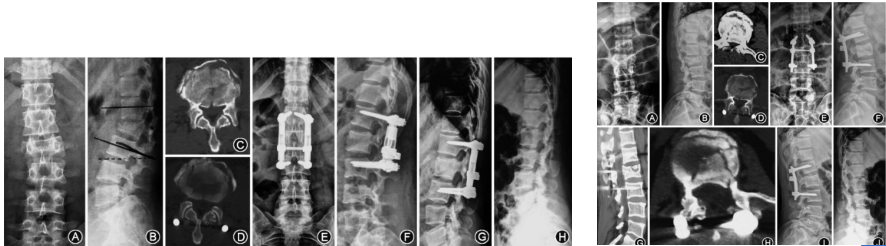

(一)开展了保留PLC连续性的椎板回植术治疗椎管内肿瘤

此项新技术,解决了为切除纵观内肿瘤造成对脊柱稳定性的破坏,国内首次提出、并开展。截止到2019年底开展手术十余例。

(四)重度强直性脊柱炎截骨矫形术